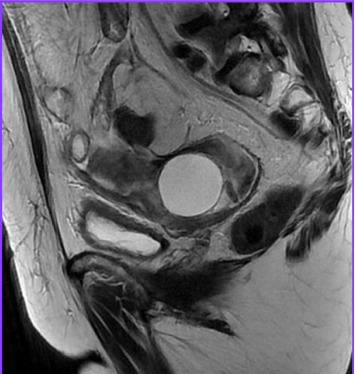

Genital tuberculosis (GT) is a rare but significant extrapulmonary tuberculosis form, often mimicking ovarian malignancy. We report a case of a 58-year-old woman with Sjögren's syndrome and rheumatoid arthritis, previously treated with infliximab, who presented with abdominal distension, weight loss, night sweats, and intermittent abdominal pain. Initial imaging and elevated CA-125 levels suggested ovarian cancer. However, intraoperative findings revealed a frozen pelvis with granulomatous inflammation, caseating granulomas, and Langhans' giant cells. Histopathological analysis and RT-PCR confirmed GT coexisting with a serous cystadenoma. GT should be considered in the differential diagnosis of pelvic masses, especially in immunocompromised patients. This case emphasizes the importance of thorough diagnostic evaluation using molecular, serological, and imaging techniques to avoid misdiagnosis and unnecessary surgical interventions. Prompt initiation of antituberculosis treatment led to significant clinical improvement. Early and accurate diagnosis of GT is crucial to prevent morbidity associated with misdiagnosis and to provide effective treatment. This case underscores the need for heightened clinical awareness and multidisciplinary approaches in managing complex cases where GT mimics malignancy, ensuring optimal patient outcomes.